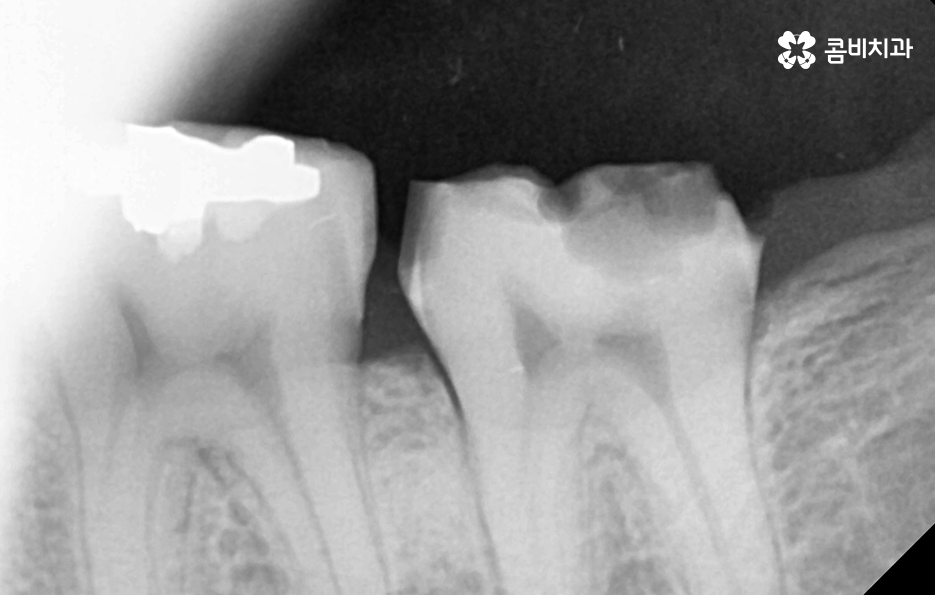

크라운 혹은 오래된 보철물 내부에 2차 충치가 발생된 경우에 자연치아를 보존할 수 있는지에 대한 판단은 엑스레이 만으로 진단할 수 있는 문제는 아니며 치아 내부에 충치가 어느정도나 진행되었고 잔존하는 치아의 양이 어느정도나 되는지에 따라서 발치 혹은 치아 보존 치료에 대한 판단을 할 수 있어요

이미 신경치료를 했던 치아라고 해도 보철물 제거 후에 충치를 잘 치료하고 재신경치료를 통해서 치아를 보존할 수 있는 경우가 있고 발치 후 임플란트를 해야하는 경우도 있는데요

이러한 판단 기준은 치아 내부에서 충치가 발생되었을 때 충치가 얼마나 치아 뿌리 쪽으로 깊어졌는지 혹은 살릴 수 있는 치아가 얼마나 잔존하는지에 따라서 다르며 치과의사 역시도 치아 속을 확인해보고 충치를 제거해봐야 알기 때문에 치과의사의 숙련도, 경험도 중요하겠지만 치과의 내원 시점이 무척이나 중요하기 때문에 보철물이 오래된 경우에는 꼭 주기적으로 치과 검진을 하시고 의사의 소견 하에 크라운의 교체가 필요하다면 문제가 커지기 전에 재치료를 적절히 받는 것이 자연치아 보존에 중요할 거예요

어금니 충치 발치 후에는 바로 임플란트를 해야 하나요

위 사진에서 보여지는 것처럼 어금니는 치아 안쪽에 위치하고 있기 때문에 치아 상실 후에 심미적인 부분에 있어서는 당장 불편함을 못느낄 수 있지만 치아는 저마다 역할과 기능이 있고 저작력에 있어서 밸런스도 무척이나 중요하기 때문에 치아를 잃게 되었다면 별다른 이유가 없다면 즉시 임플란트 치료 계획을 세우시길 권하고 있어요